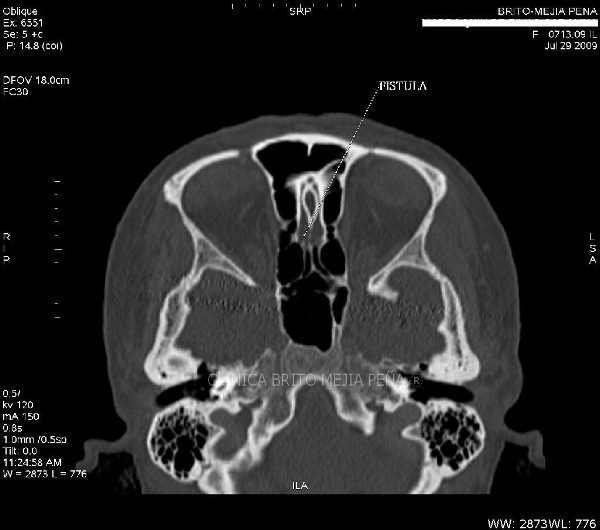

Fístula LCR axilar

Fístula LCR sagital

Fístula LCR coronal